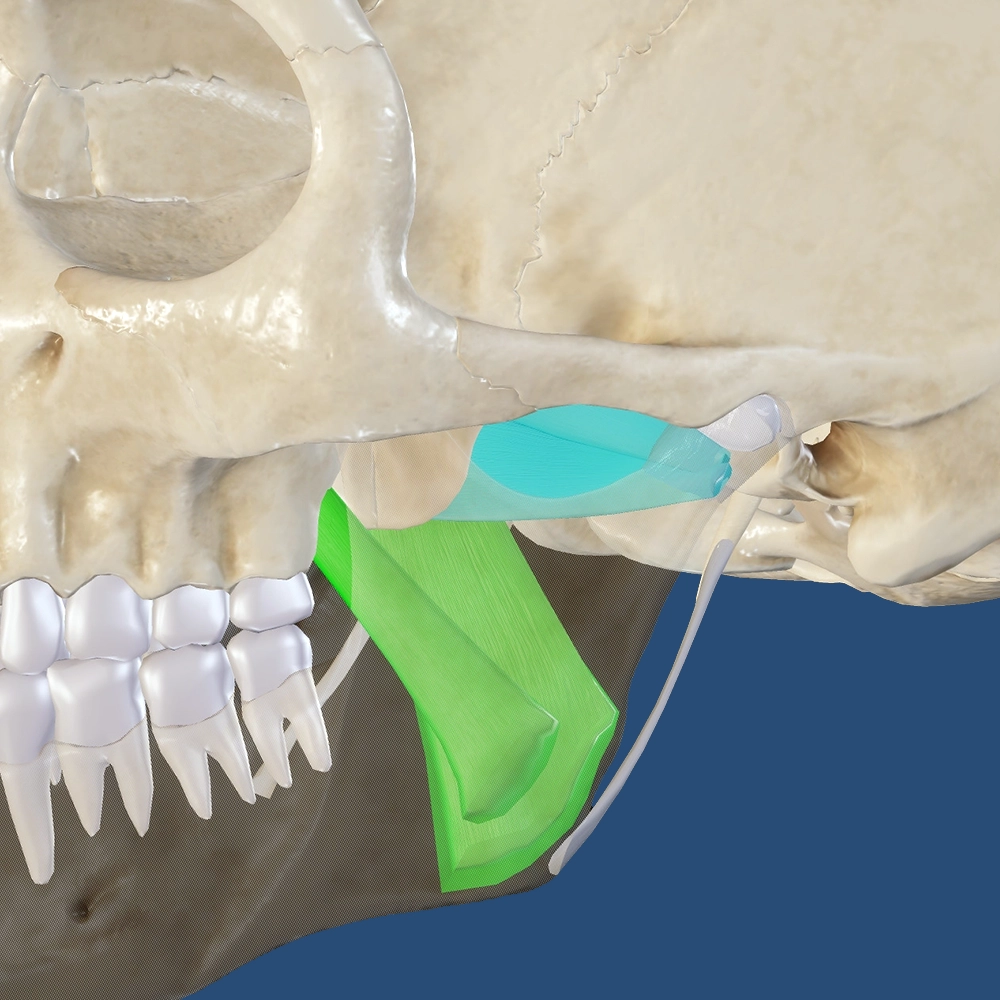

Misaligned jaws can make everyday activities like eating feel frustrating and uncomfortable. Patients may struggle to chew effectively, which can lead to digestive issues and lower quality of life. Corrective jaw surgery restores proper alignment, making eating more comfortable and enjoyable. Choosing Maine Oral Surgery & Dental Implant Center gives you the opportunity to reclaim functional oral health and confidence during meals.